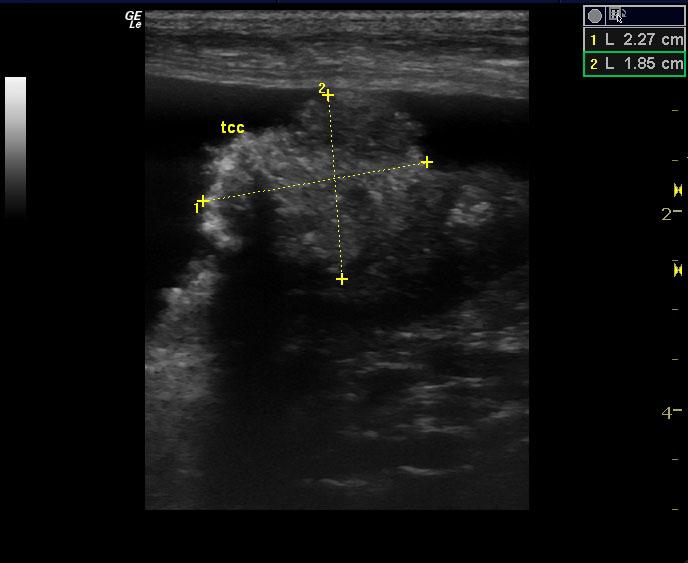

A 10-year-old SF American Eskimo with a history of bladder transitional cell carcinoma that had been stented, chronic renal insufficiency, hydronephrosis, and hydroureter, was presented for evaluation. CBC showed anemia (14%).